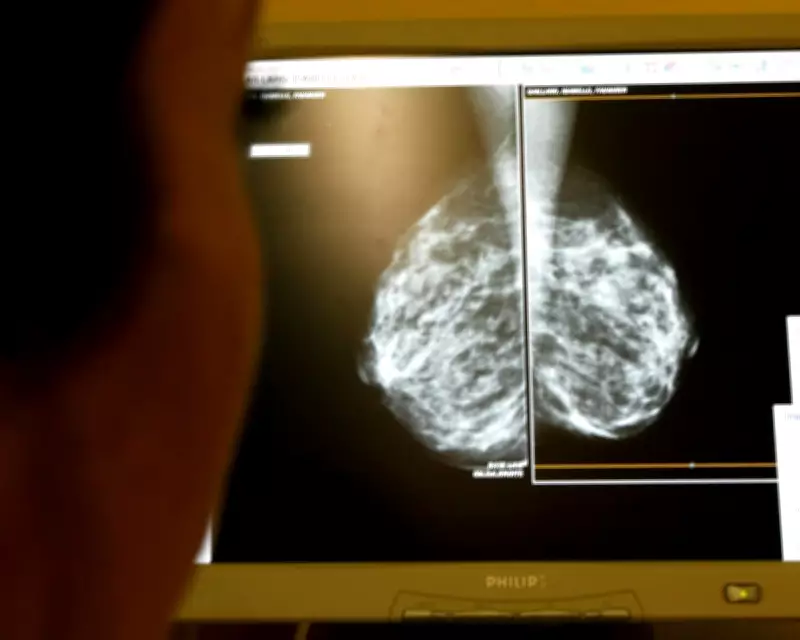

The trial, conducted between April 2021 and December 2022, randomly assigned participants to either AI-supported screening or standard double reading by two radiologists. The AI system analysed mammograms, directing low-risk cases to a single radiologist review and high-risk cases to a double reading, while also highlighting suspicious findings to assist medical professionals. This innovative approach aimed to streamline the screening process without compromising accuracy.

The results, published in The Lancet, demonstrated a clear advantage for AI-supported screening. In the AI group, cancer incidence was 1.55 per 1,000 women, compared to 1.76 per 1,000 in the control group. More strikingly, 81% of cancers in the AI-supported group were detected at the screening stage, versus 74% in the control group. Additionally, the AI group showed a 27% reduction in aggressive subtype cancers, indicating a potential for identifying more dangerous forms of the disease earlier.